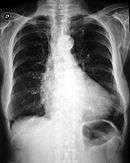

Hypoglycemia in early infancy can cause jitteriness, lethargy, unresponsiveness, or seizures.[4] The most severe forms may cause macrosomia in utero, producing a large birth weight, often accompanied by enlargement of the heart (cardiomegaly) and liver. Milder hypoglycemia in infancy causes hunger every few hours, with increasing irritability or lethargy if feeding is delayed.Congenital hyperinsulinism often becomes apparent later via an inability to sleep through the night. Sometimes an unusual stress like an illness precipitates a severe hypoglycemic episode.Milder forms have occasionally been detected by investigation of family members of infants with severe forms. Adults with the mildest degrees of congenital hyperinsulinism may simply have a decreased tolerance for prolonged fasting.